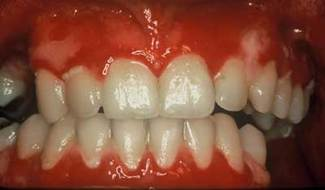

Clinical impressions: As you begin your oral assessment, you note the buccal mucosa and gingiva are erythematous with some ulceration and erosion. The erythema is very prominent at most marginal gingival areas. The tissue bleeds with very little pressure (see figure 1). You also notice that his lips appear ulcerated and crusted (see figure 2).

Early treatment is crucial in controlling pemphigus vulgaris. Sirois, et al. (2000) reported that more than 50 percent of patients in their study sought initial care from their dental clinician. Just as pemphigoid (March 2007) is often characterized as desquamative gingivitis (a general term), this is true also for pemphigus vulgaris depending upon the severity of the disease. The tissue involved is erythematous and ulcerated (see figure 1). Bullae may be present and they rupture to form painful erosions. The borders of the erosions are often ragged and painful. Depending upon the type of pemphigus, the lesions may appear to have vegetations or scales on the surface.